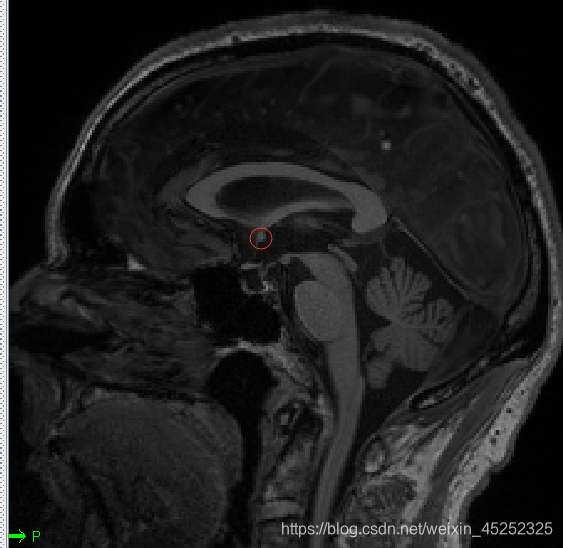

一般的nii图中各组织并不是这么明显

(2) 第一个目标标记AC上中部和后中部

AC:

•矢状位:在穹窿下方胼胝体底部寻找AC

① 使AC在十字准线的焦点处居中(轴向和冠状)

② 向上移动,直到AC在轴向视图中消失,然后向下移动1像素

③ 设置AC上边缘(superior edge)

④ 将焦点移回AC中间

⑤ 向后移动直到AC在冠状面上消失;然后往前1像素

⑥ 设置AC后缘(posterior margin)

尽量把图放大来选点

找到AC superior edge,点击set

找到AC posterior edge,点击set